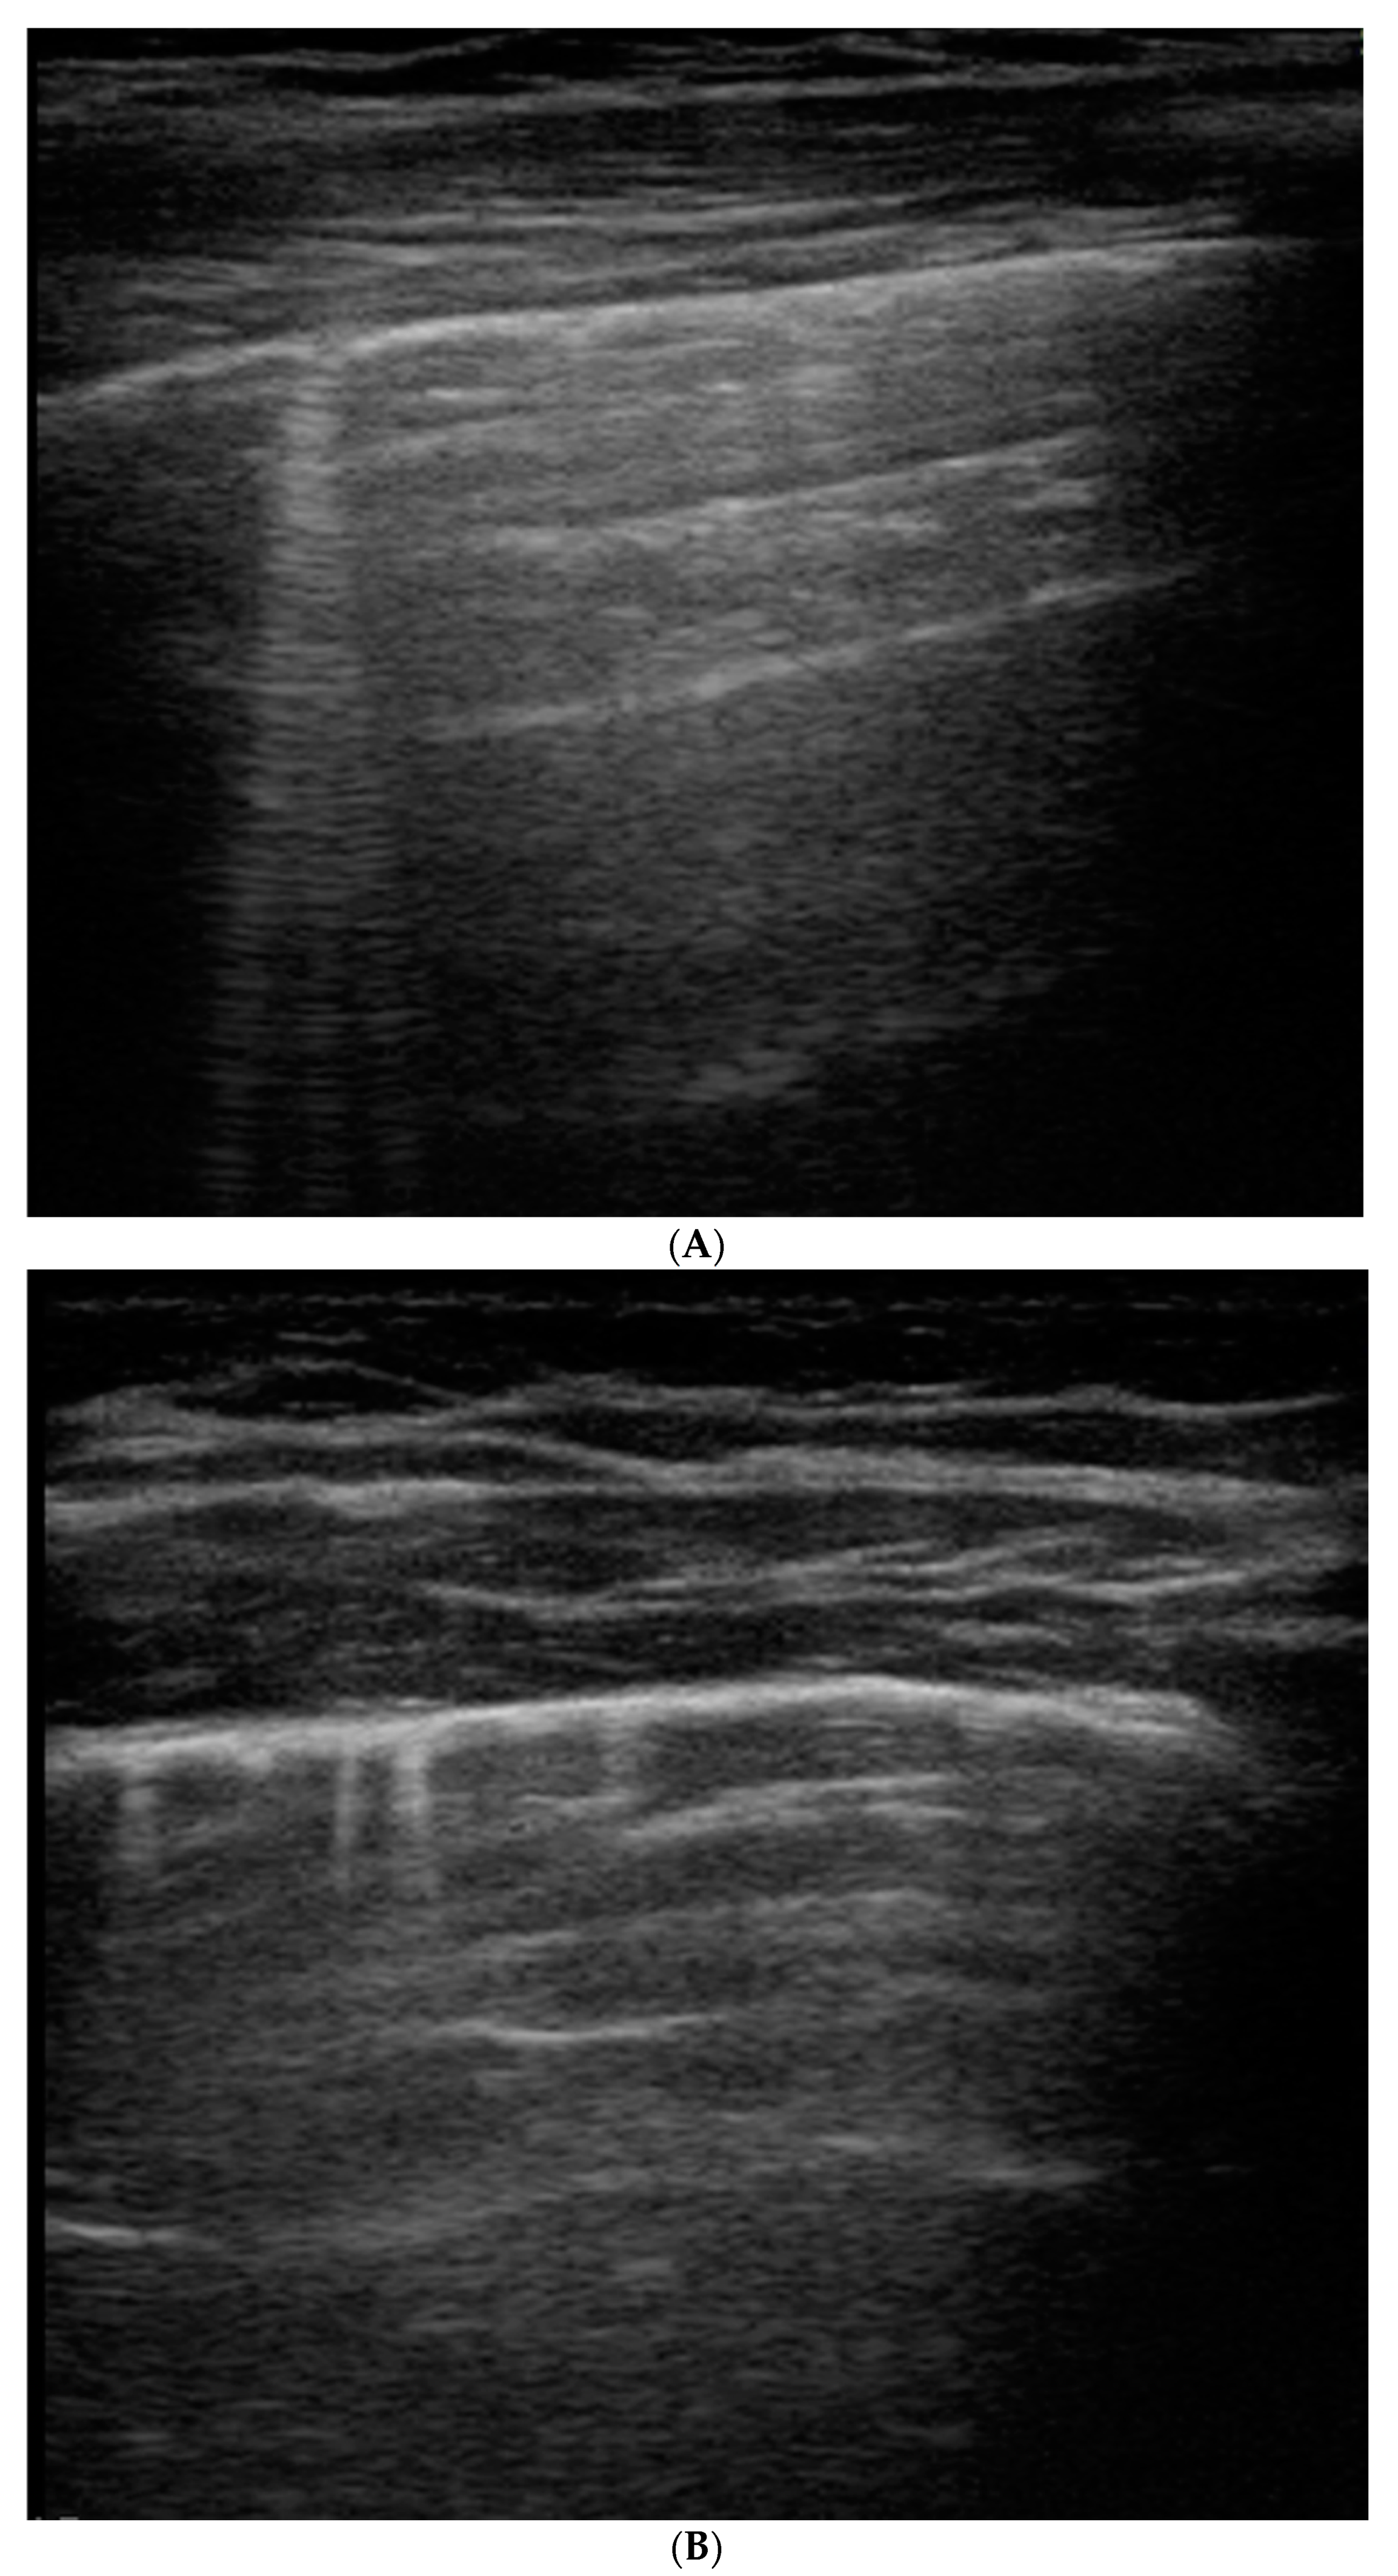

- Seashore sign (lateral): echogenic pleural line divides the image in the motionless part represented by horizontal lines (sea waves) and the part below that appear granular (sand) as the normal to-and-from motion of the lung is reflected over that area (normal lung sliding).

- Barcode sign (central): absence of a dynamic image, substituted by a static posterior acoustic shadowing (horizontal lines).